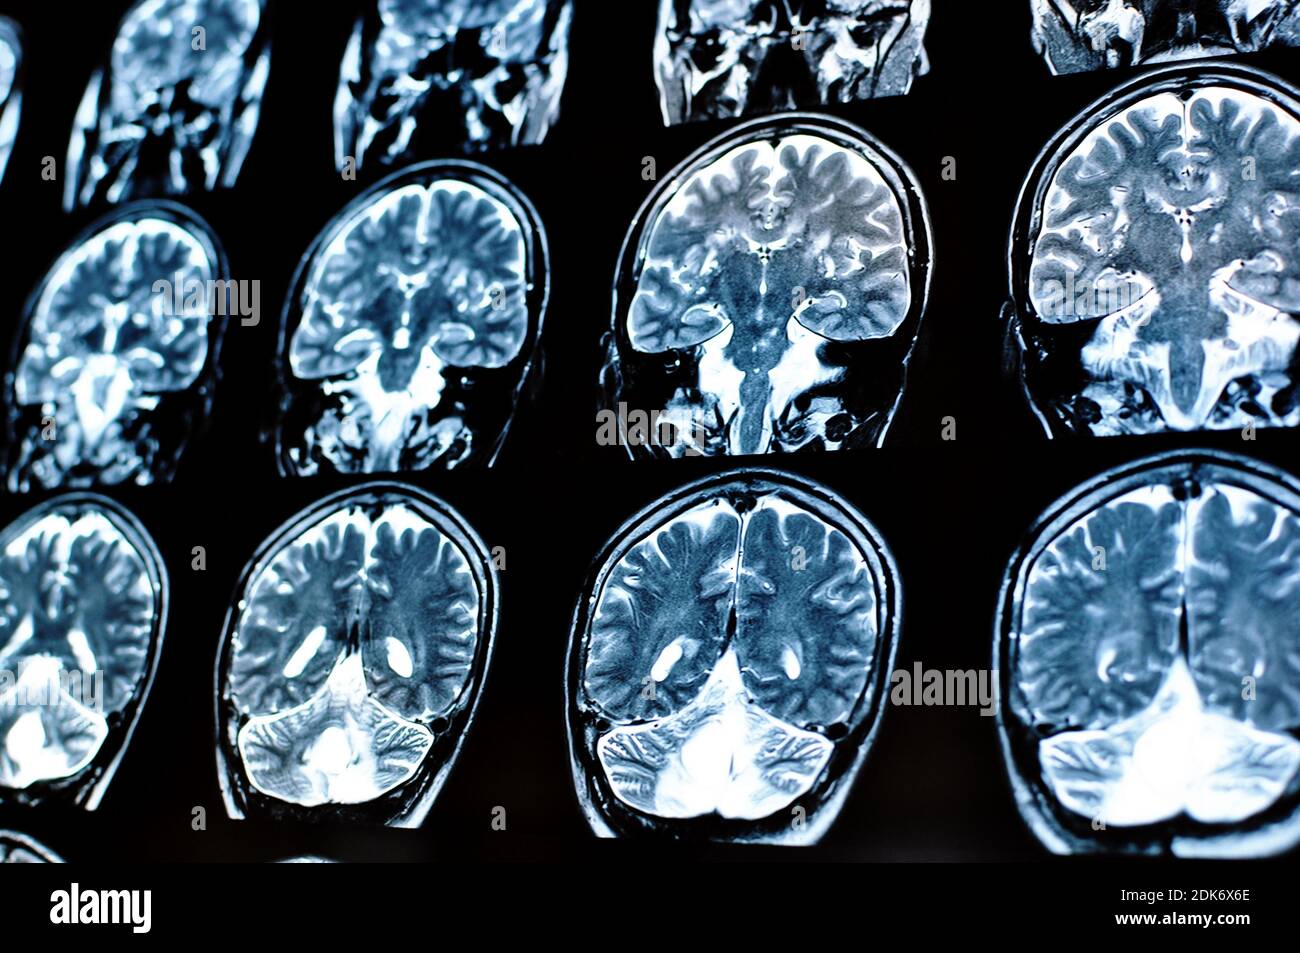

Acquisition d'image par résonance magnétique d'un cerveau humain avec un kyste colloïde. Film IRM d'une tumeur du cerveau et du crâne humain. Antécédents de neurologie. Médecine, science. Banque D'Imageshttps://www.alamyimages.fr/image-license-details/?v=1https://www.alamyimages.fr/acquisition-d-image-par-resonance-magnetique-d-un-cerveau-humain-avec-un-kyste-colloide-film-irm-d-une-tumeur-du-cerveau-et-du-crane-humain-antecedents-de-neurologie-medecine-science-image390458838.html

Acquisition d'image par résonance magnétique d'un cerveau humain avec un kyste colloïde. Film IRM d'une tumeur du cerveau et du crâne humain. Antécédents de neurologie. Médecine, science. Banque D'Imageshttps://www.alamyimages.fr/image-license-details/?v=1https://www.alamyimages.fr/acquisition-d-image-par-resonance-magnetique-d-un-cerveau-humain-avec-un-kyste-colloide-film-irm-d-une-tumeur-du-cerveau-et-du-crane-humain-antecedents-de-neurologie-medecine-science-image390458838.htmlRF2DK6X6E–Acquisition d'image par résonance magnétique d'un cerveau humain avec un kyste colloïde. Film IRM d'une tumeur du cerveau et du crâne humain. Antécédents de neurologie. Médecine, science.